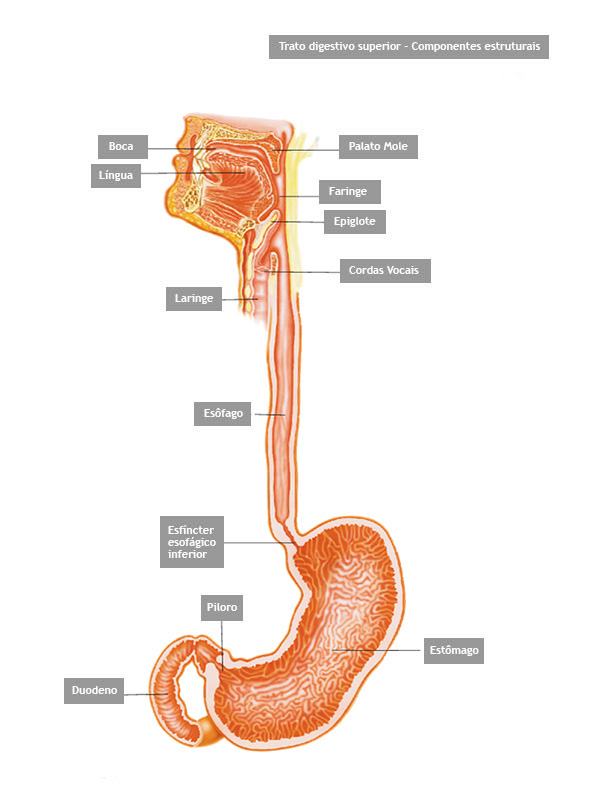

É um exame indicado para avaliação diagnóstica e tratamento das doenças da parte superior do tubo digestivo, incluindo o esôfago, o estômago e a porção inicial do duodeno.

Realizado introduzindo-se pela boca um aparelho flexível com iluminação central que permite a visualização de todo o trajeto examinado.

O esôfago é um tubo longo e estreito que transporta comida e líquidos da boca para o estômago.

O que é o piloro ?

Piloro é o esfíncter que fica na poção final do estômago, na sua transição com o duodeno. Com os movimentos de contração do estômago o piloro se abre a permite que o conteúdo estomacal passe para o duodeno.

O que é?

É um exame indicado para avaliação diagnóstica e tratamento das doenças da parte superior do tubo digestivo, incluindo o esôfago, o estômago e a porção inicial do duodeno.

Realizado introduzindo-se pela boca um aparelho flexível com iluminação central que permite a visualização de todo o trajeto examinado.